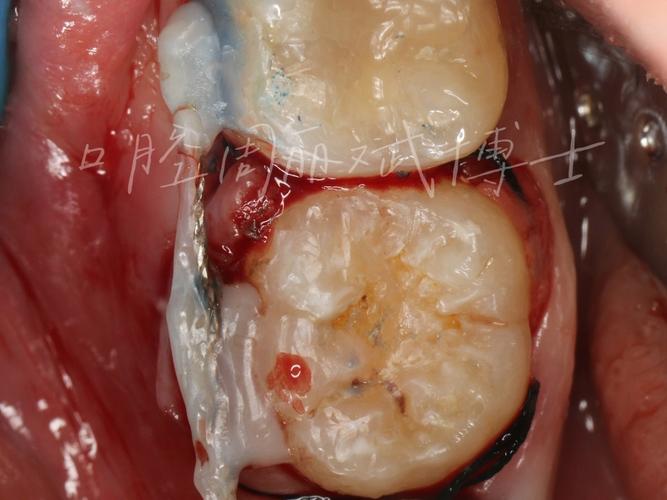

手术流程需严格遵循无菌原则和精准操作,通常分为术前准备、取骨、移植及种植体植入四个阶段,术前评估是基础,通过CBCT三维成像测量缺牙区骨高度、宽度及密度,判断骨缺损类型(垂直缺损、水平缺损或复合缺损),同时检查供区骨量及健康状况,取骨操作中,颏部取骨需沿下颌外斜线做切口,剥离骨膜后显露颏部外板,用超声骨刀截取所需大小骨块,注意保护颏神经;髂骨取骨则需在髂嵴做弧形切口,显露髂骨内外板,根据需要取骨块或骨颗粒,移植阶段,将获取的骨块修整成与受区匹配的形状,用钛钉或钛板固定于缺牙区骨面,确保与周围骨紧密贴合;若采用骨颗粒移植,则需与自体血液混合后植入,覆盖可吸收胶原膜防止软组织侵入,种植体植入可在自体骨移植同期进行(即刻种植),也可在骨愈合3-6个月后延期植入,前者可缩短治疗周期,但对初期稳定性要求较高,后者则需二次手术,但骨整合更充分。